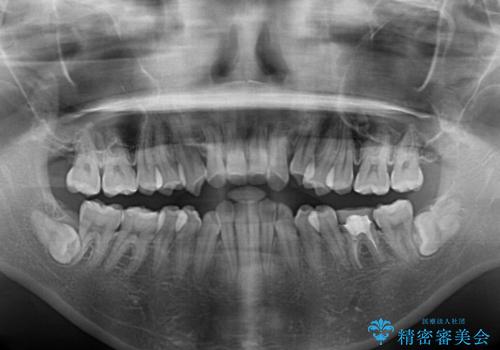

- 上の前歯の飛び出した感じを改善したいとのことで来院された患者様です。

上顎左右第一小臼歯2本、下顎左右第二小臼歯2本を抜歯し、ワイヤー装置にて口元を引っ込めるよう矯正治療を行うこととしました。

上下の前歯に隙間が空くほど上顎前歯が前に飛び出していましたが、抜歯矯正により上下前歯がぴったりと付くほど口元を引っ込めることができました。